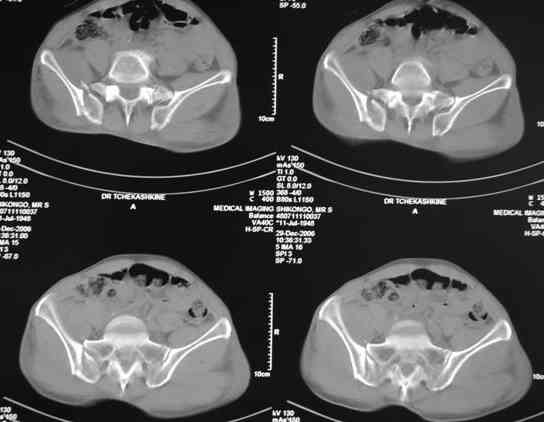

В приложении отправляю послеопер. снимки бедра и лодыжки обсуждаемого вчера больного.

В приложении послеоперационные картинки.